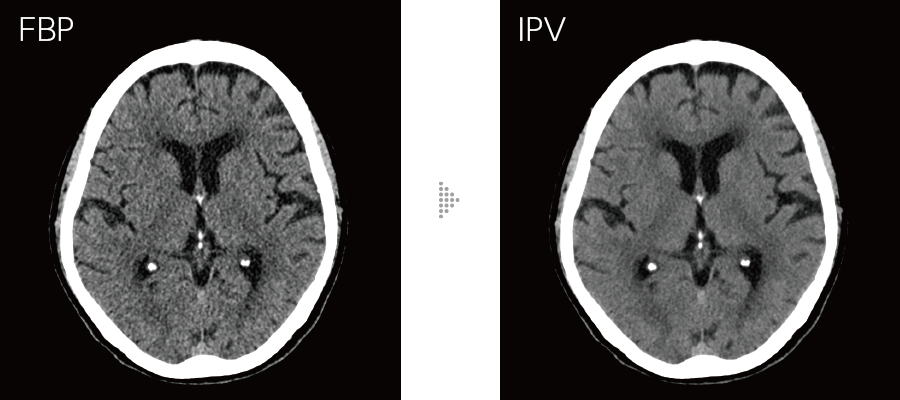

Our iterative reconstruction method, Intelli IPV, provides images that maintain their natural texture even at high noise reduction rates and their excellent visibility even at low doses, and does not require a dedicated operating room or additional hardware.

While adjusting the texture at a uniform ratio from high frequency to low frequency, the physical properties that affect visibility are made as close as FBP.